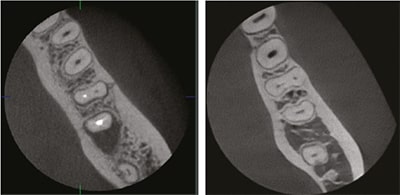

Высокоточный ENDO режим

В режиме Endo объем сканирования составляет 4x4 см, а размер вокселя равен 49,5 микрометрам. Это позволяет получать изображения высокой четкости, что идеально подходит для эндодонтической практики. Стоматологи могут детально исследовать интересующую зону с максимальным разрешением, что особенно важно для точного и эффективного лечения.